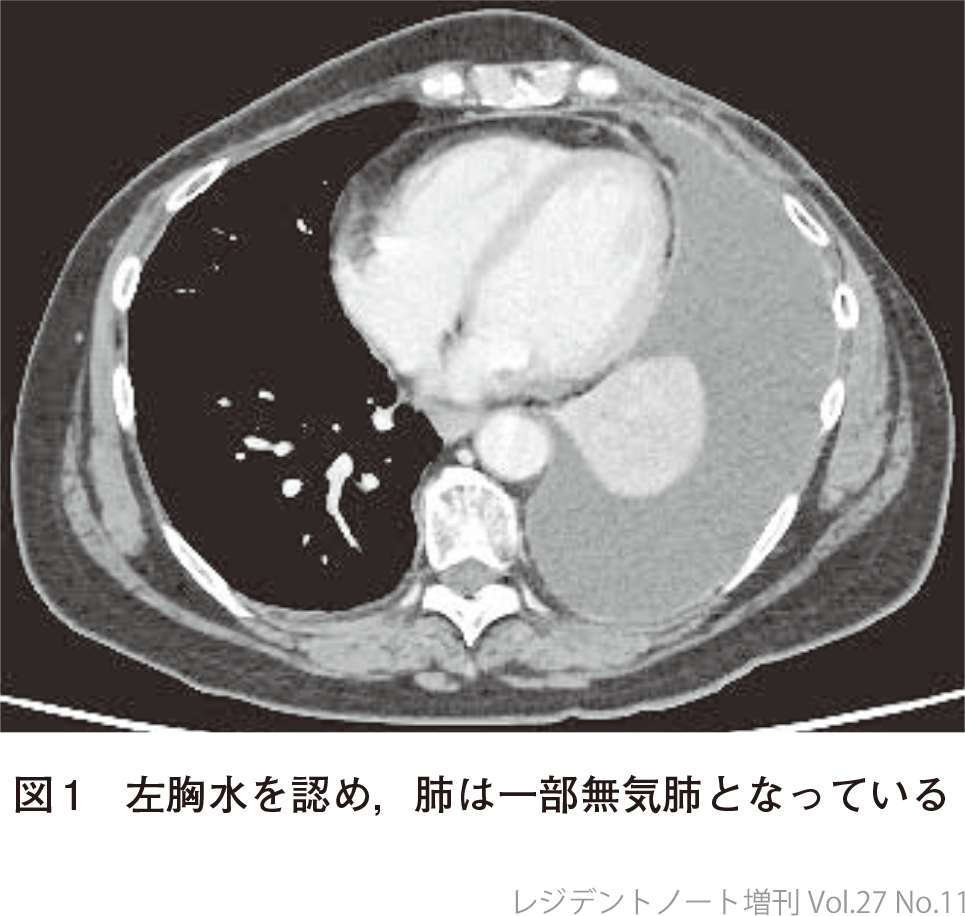

64歳女性.ホルモン受容体陽性乳がんの術後フォロー中に左胸水を指摘され,PET(positron emission tomography:陽電子放出断層撮影)CT検査で多発リンパ節転移と多発骨転移を認めた.頸部リンパ節生検でホルモン受容体陽性乳がん再発の診断となり,レトロゾール+パルボシクリブ内服を開始.治療開始12カ月後のCT検査で左胸水増加を認め(図1),労作時息切れの訴えがあった.

悪性胸水の診断で,胸水以外の病変は増大なく経過していたことから胸膜癒着術を施行する方針とした.胸腔ドレーンを挿入して連日排液を行い,十分に排液できたことを確認してタルクで胸膜癒着術を施行.その後も胸水増加みられず,胸腔ドレーンは抜去.以降も胸水増加なく経過している(図2).